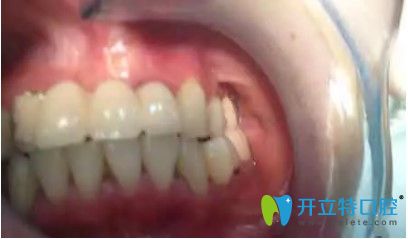

在拆除烤瓷橋后,發(fā)現(xiàn)她的口內(nèi)埋伏牙,把埋伏牙拔除后,很順利的植入了種植體,完成了種植牙。

劉女士反饋,自己很后悔當(dāng)初做了烤瓷牙,她表示,自己對(duì)韓國(guó)的種植牙技術(shù)很認(rèn)可,所以來(lái)韓國(guó)做了種牙手術(shù)。